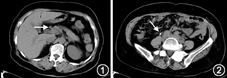

进一步完善相关检查:抗溶血性链球菌素O 27.6 IU/ml;补体C3 0.647 g/L(参考值:0.73~1.46 g/L),补体C4 0.217 g/L;ANA、抗ENA抗体、ANCA、抗GBM抗体均阴性;IgG 17.13 g/L(参考值:7.00~17.00 g/L),IgA 1.14 g/L,IgM 0.50 g/L;总IgE 187 kU/L(参考值:0~60 kU/L);血清蛋白电泳、血免疫固定电泳未见单克隆蛋白。胸腹盆CT:部分纵隔淋巴结稍肿大;胰头饱满,胆总管增宽;左肾增大,双肾积水(轻中度);双侧髂动脉、输尿管盆段周围软组织密度影,腹膜后纤维化不除外(图1、图2)。磁共振尿路成像MRU:双侧尿路梗阻,肾盂输尿管积水,梗阻位于小骨盆入口处第二狭窄,右肾形态及信号异常(凹凸不平,体积缩小,肾实质变薄,皮髓质分界不清)。